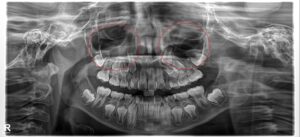

赤丸の部分が上顎洞です

鼻の両脇、上の奥歯の根元の辺り、頭蓋骨の中に鼻と通じた上顎洞という空洞があります。

この上顎洞の内面の粘膜が炎症を起こします。

これを上顎洞炎(じょうがくどうえん)といいます。副鼻腔炎のひとつです。

上アゴ奥歯の根の先端が、この上顎洞に非常に近い為、歯が原因ではない、奥歯に何も異常がない場合でも、上顎洞炎が起きると噛むという動作で響く痛みを感じる症状が現れます。